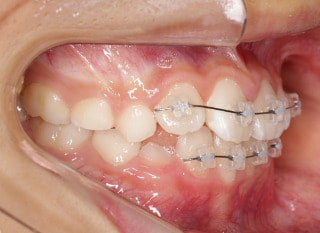

小児期第二段階

開始時